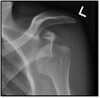

Anterior or posterior dislocation?

Anterior dislocation